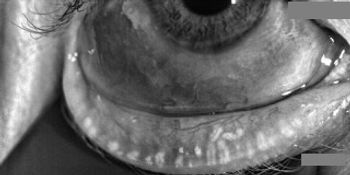

Patients deserve to have their tear film stabilized before surgery so their vision will be optimized after surgery.

Failure to address problems with the tear film and ocular surface before surgery can negatively affect surgical outcomes and patient satisfaction.

IPL’s mechanism of action a useful tool in treating underlying causes of chalazia, according to Laura M. Periman, MD.